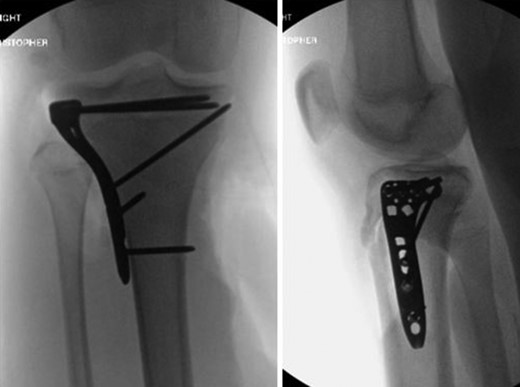

Patient is a 14-year-old male who slipped and fell while jumping off of a diving board and landed onto a flexed right knee. The patient was stable on presentation and neurovascularly intact with the knee locked in flexion. Skin was tenting anteriorly over the tibial tubercle and his compartments were swollen but compressible. A single plain film view (Fig. 1) was obtained prior to orthopaedic consultation. Closed reduction under sedation and splitting was attempted in the ED with partial but unsatisfactory improvement. Post-reduction radiographs (Fig. 2) demonstrated a tibial tubercle fracture with extension through the entire proximal tibial physis with metaphyseal involvement posteromedially. We classified this as a type IV tibial tubercle fracture, Salter–Harris II variant. In conjunction with patient and family we planned for urgent closed versus open reduction and application of knee-spanning external fixator. Immediately prior to surgery in the pre-operative holding area, the patient noted increasing right leg pain. In the operating room (OR), a marked increase in swelling with tense skin was observed. Due to rapidly progressive swelling and nature of the fracture, the decision was made to proceed with a 4-compartment fasciotomy of the right leg. The medial-sided fasciotomy (Fig. 3) revealed significant bulging of the superficial and deep compartments; however, the anterior and lateral compartments were less swollen. The fracture was unable to be closed reduced intraoperatively, therefore proximal extension of the medial fasciotomy wound was performed to open and reduce the fracture under direct visualization. Anatomic reduction was achieved and a knee-spanning external fixator was applied (Fig. 4). Approximately 72 hours later the patient was brought back to the OR for irrigation and debridement, lateral wound closure, and medial wound vacuum placement. Another 72 hours later, he returned to the OR for removal of the external fixator, ORIF, and split-thickness skin grafting of the medial fasciotomy site. An anterolateral approach was used with a 3.5 mm proximal tibial locking plate (Fig. 5). At most recent follow-up (Fig. 6), six months post-op, the patient is pain free, ambulating without assistive device, and has returned to all desired activities.

Presenting plain film view demonstrating proximal tibia fracture.

AP and lateral intraoperative fluoroscopic images following ORIF with proximal tibial locking plate.